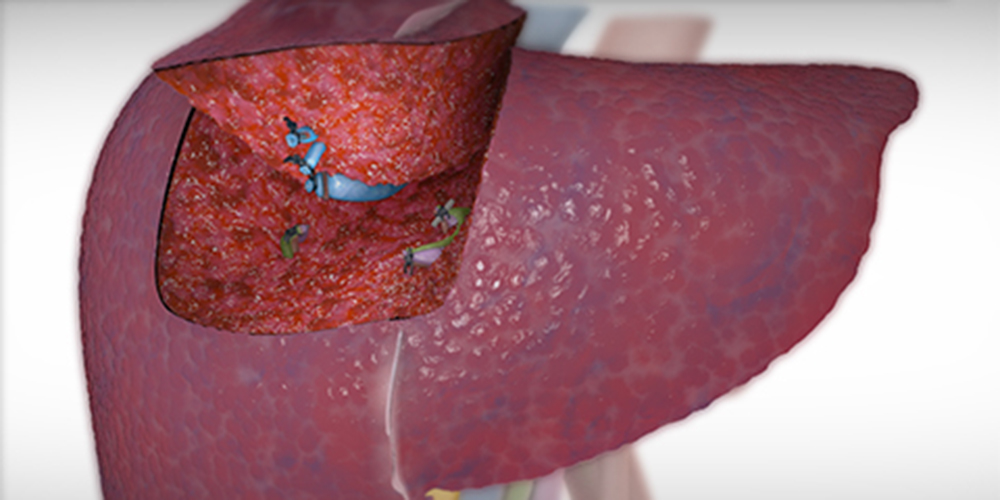

Nowotwór wątroby to złośliwy nowotwór występujący w tkankach wątroby lub jej drogach żółciowych. Może rozwijać się na skutek przerzutów innych nowotworów do wątroby lub jako rak wątrobowokomórkowy. Najczęstsze przyczyny raka wątroby to zakażenia wirusowe, nadmierne spożywanie alkoholu, narażenie na toksyny czy inne szkodliwe czynniki. Objawy raka wątroby mogą być niecharakterystyczne, dlatego kluczowe jest wcześniejsze rozpoznanie dla skutecznego leczenia.

Badania obrazowe, takie jak ultrasonografia (USG), tomografia komputerowa (TK) i rezonans magnetyczny (RM) są wykorzystywane do wykrywania nowotworów wątroby.

- USG może być często wykonywane jako pierwsze badanie, ponieważ jest powszechnie dostępne i nieinwazyjne. Może pomóc w wykryciu guzów oraz ocenie struktury wątroby i przepływu krwi.

- TK i RM dostarczają bardziej szczegółowych obrazów anatomicznych i mogą być używane do oceny stopnia zaawansowania nowotworu.